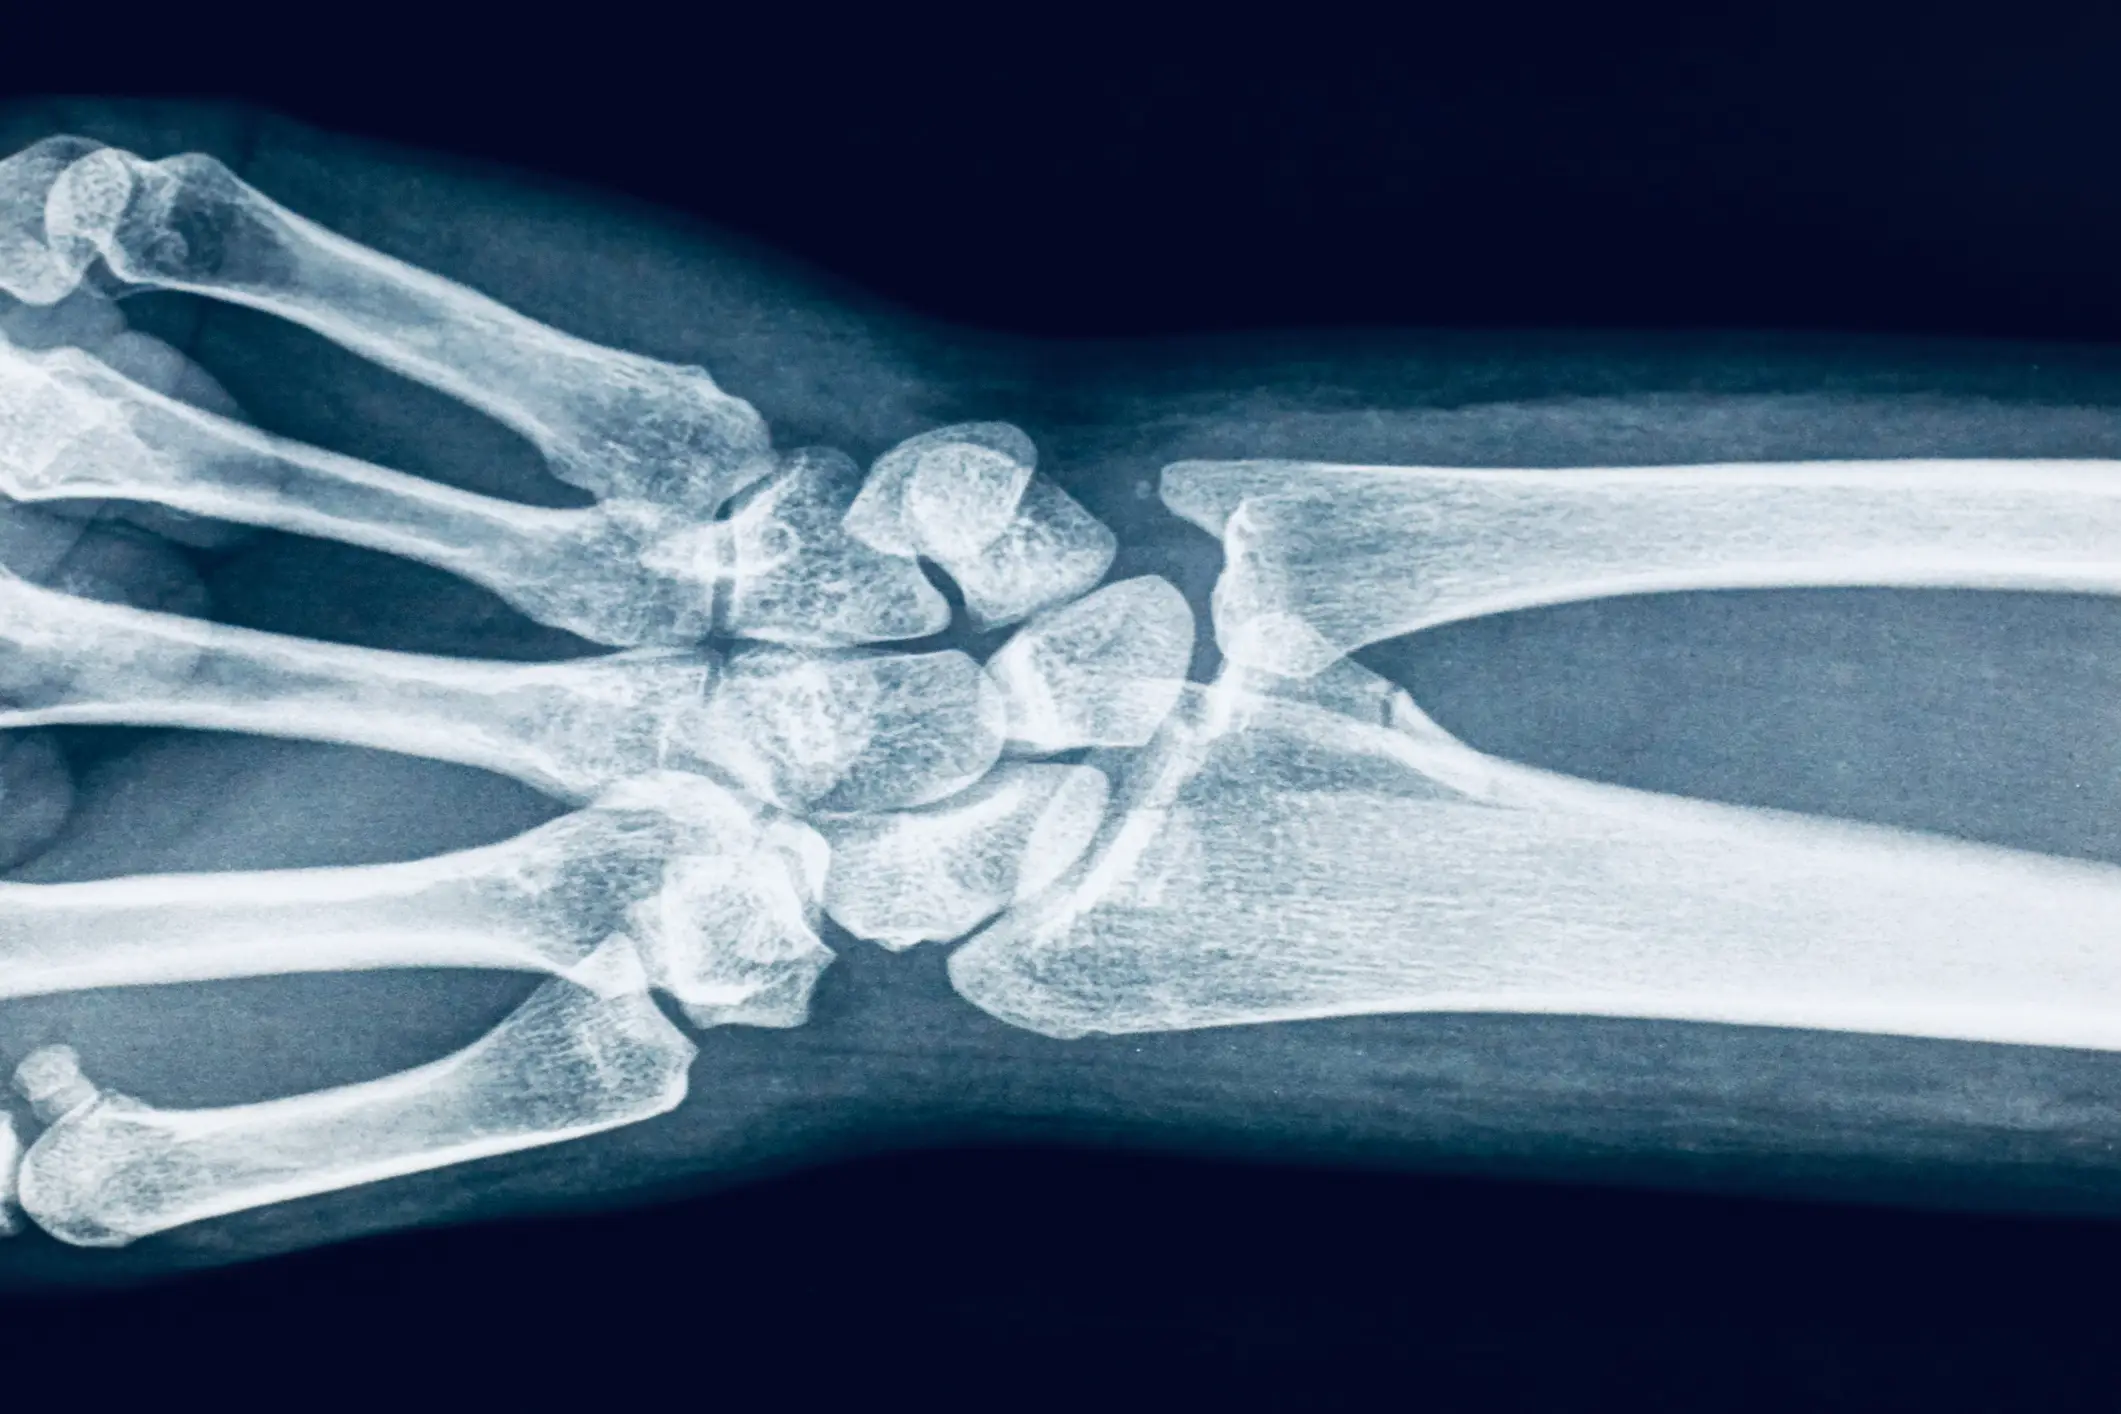

After receiving comments urging him to get checked, @Razzooz thanked his followers and everyone else who reached out about his health in a follow-up video, revealing he works as an X-ray technician.

"You guys noticed that I have this white streak on my fingernail and pointed out the fact that that could actually be a sign of skin cancer."

"The fact that TikTok is the reason I found out about this or that I'm an X-ray tech," then revealing the index is the finger he uses to start the X-ray machine.